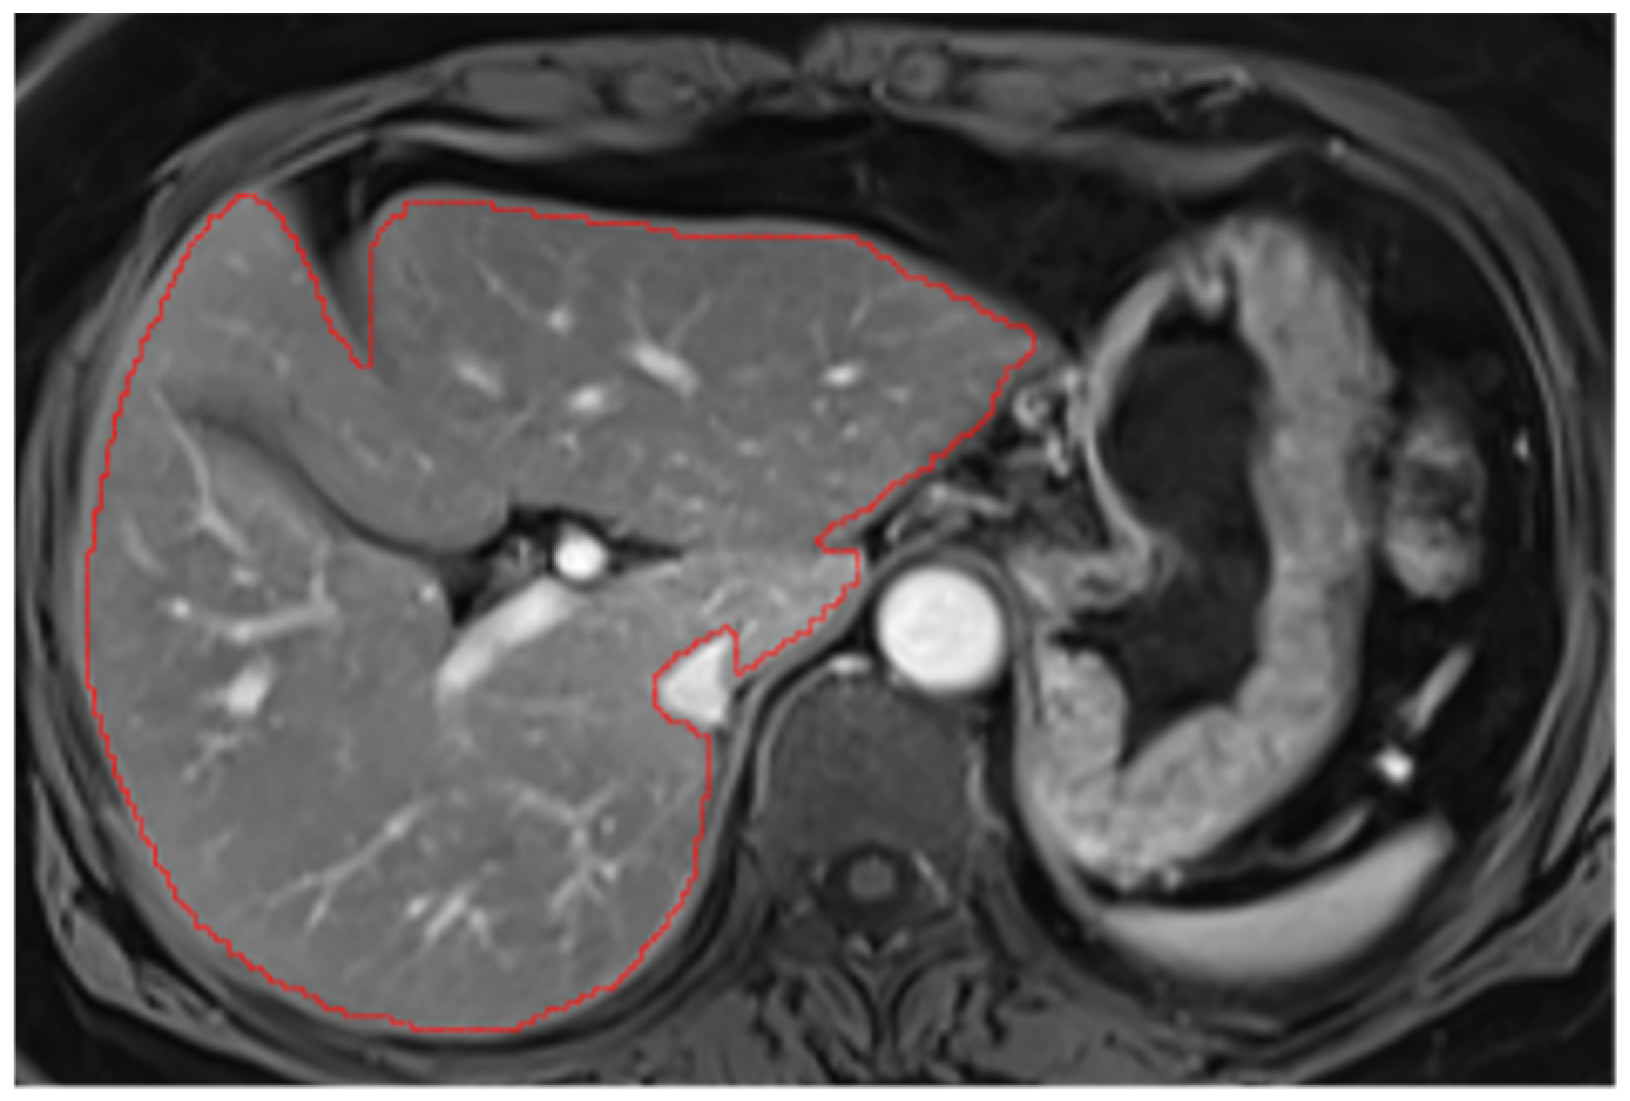

Appendix A.3. Vascular Segmentation